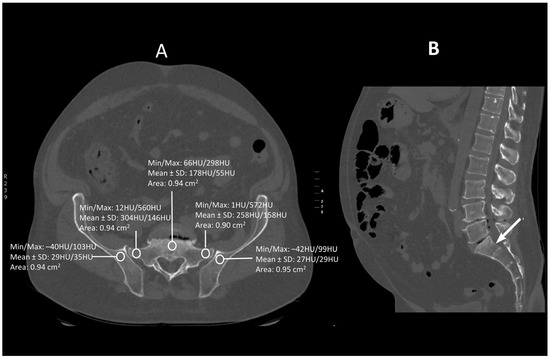

Figure 1.

A transverse (A) and saggital (B) projection of CT scan in level S1. A circular region of interest (ROI) ranging from 0.8 to 1.2 cm2 has been placed at the ala of the ilium, the wing of the sacrum and the body of sacral vertebra 1.

Images were viewed using the bone algorithm default windows. The investigator first determined axial images in levels of mid-lengths of bodies of sacral vertebrae 1, 2 and 3 that afterward were confirmed by coronal and sagittal reconstructions (Figure 1, Figure 2 and Figure 3). The volumetric bone density expressed in HU values was measured in sacral levels of S1, S2 and S3. Apart from the bodies of sacral vertebrae S1–S3, the measurements involved the ala of the ilium in the vicinity of the sacroiliac joint and the wing of the sacrum. All the measurements were performed on the pathway of presumptive iliosacral screws to stabilize the sacroiliac joint.

In order to standardize measurements while accounting for normal anatomic variations and optimum iliosacral screw trajectories—so as to avoid injuries of neurovascular structures—standardized circular voxel regions of interest (ROIs) were drawn (Figure 1, Figure 2 and Figure 3) [12]. As presented in the former studies, these ROIs were drawn in levels of mid-lengths of the bodies of sacral vertebrae 1, 2 and 3, the right and left wings of sacrum and the ala of the ilium in sacral levels of S1–S3 [13]. The aforementioned standardized ROIs were drawn with areas ranging from 0.8 to 1.2 cm2. This range of area was estimated as it best represented the osseous surface area, which is required to safely place 7.0–mm iliosacral or transsacral screws [4].